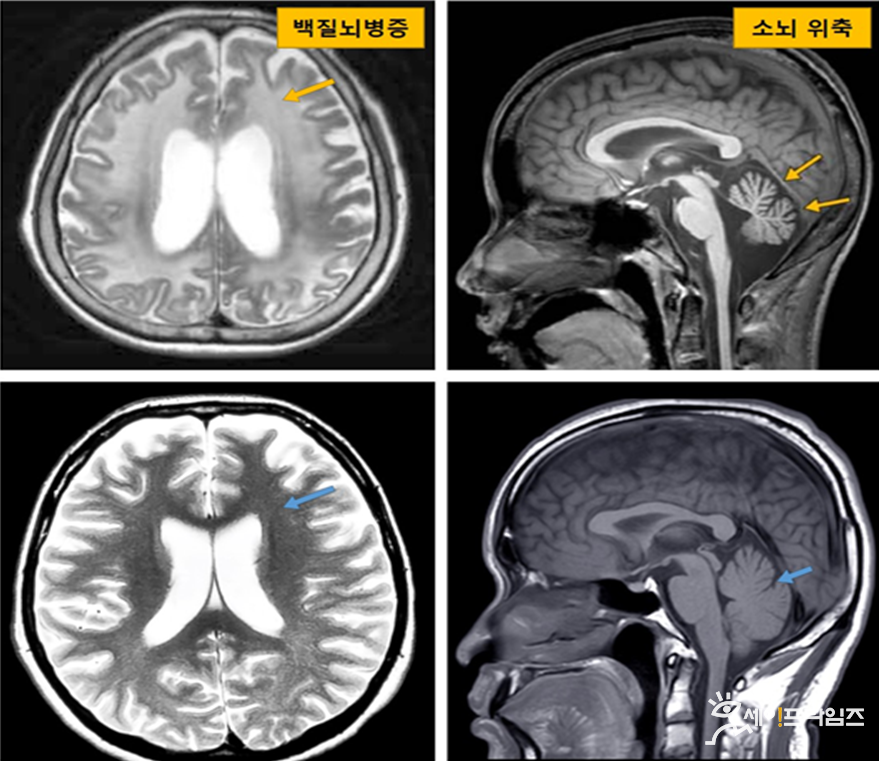

이를 활용해 서울대병원에 내원한 원인불명 백질뇌병증 환자 90명 중 신경세포핵내봉입체병 영상 소견이 있는 환자의 전장유전체 데이터 분석을 진행했다.

그 결과, 16명(17.8%)에서 단연쇄반복 변이가 확인됐다. 즉 국내 원인불명 백질뇌병증 환자 10명 중 1~2명은 희귀질환 신경세포핵내봉입체병을 앓고 있다.